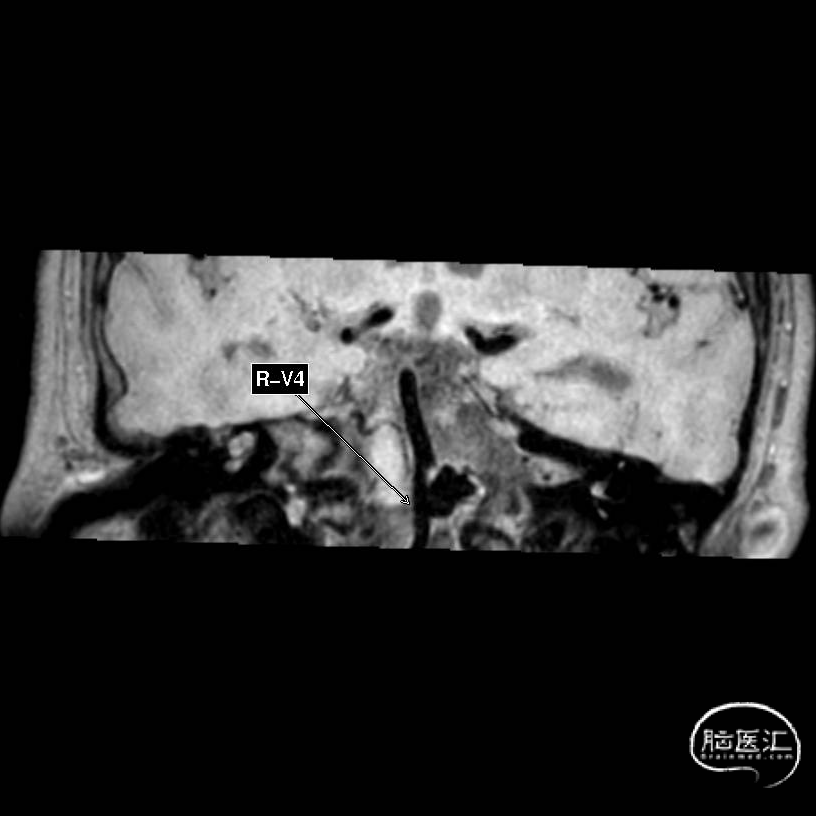

患者女性,75岁 。

主诉:突发意识障碍后头痛、头晕2天。

现病史:入院前2天,患者无明显诱因出现意识障碍后摔倒,伤致头枕部,约20多分钟后患者逐渐清醒,诉头痛、头晕,无呕吐,无大小便失禁,无肢体偏瘫等症状,遂由家属联系120送入当地医院,完善头部CTA后提示:椎动脉V4段动脉瘤伴蛛网膜下腔出血,现为求进一步治疗就诊于我院急诊,急诊以“蛛网膜下腔出血”收入我科。

经测量可得动脉瘤宽度平均值为7.0mm,动脉瘤高度为7.4mm,最终选择WEB™ SL 9*6。

动脉瘤远端子囊先进行填圈,近端动脉瘤植入WEB™。

术后6个月影像提示血栓形成,动脉瘤完全闭塞,WEB™完全栓塞。